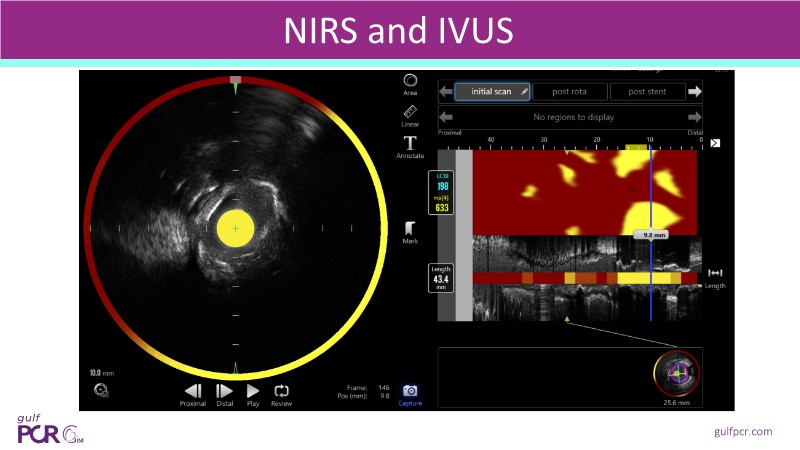

This session explores how near-infrared spectroscopy (NIRS) is redefining PCI by revealing what angiography cannot see. By identifying lipid-rich and vulnerable plaques, NIRS helps anticipate procedural risk and refine decision-making before stent implantation. The session shows how plaque composition, rather than calcium alone, can guide lesion preparation strategies, support safer stent positioning, and improve expansion. Through practical examples, it highlights how integrating NIRS with intravascular imaging and physiology moves PCI toward a more targeted, data-driven, and truly precision-based approach.

- To identify vulnerable plaques: NIRS detects lipid-rich plaques that are invisible to angiography. This allows interventionalists to anticipate complications like distal embolisation or no-reflow and adjust their approach accordingly

- To optimise lesion preparation: when NIRS reveals high lipid burden or calcific nodules, operators can choose atherectomy, intravascular lithotripsy, or specialised balloons to modify the lesion before stenting

- To improve stent placement and expansion: NIRS-IVUS guidance ensures stents are deployed in stable segments, avoiding lipid-rich or heavily calcified areas that may compromise expansion or healing